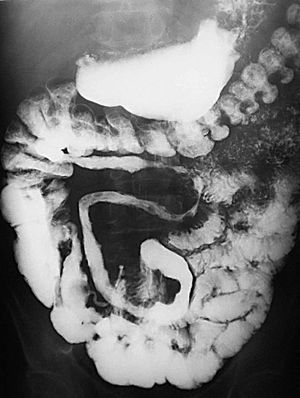

Al nivel de íleon terminal el espasmo justifica el signo de "la cuerda" (fig. 6). En relación no sólo con el espasmo, sino con una proliferación fibroadiposa del mesenterio aparece el signo del "asa orgullosa" en el estudio con bario, cuyo sustrato fisiopatológico ilustra la TC (fig. 7).

Fig. 7.--Enfermedad de Crohn, fase activa inflamatoria. (A) Signo del "asa orgullosa" en el tránsito intestinal. (B) Correlación tomodensitométrica: separación del asa intestinal del resto en relación con proceso inflamatorio de la grasa mesentérica.